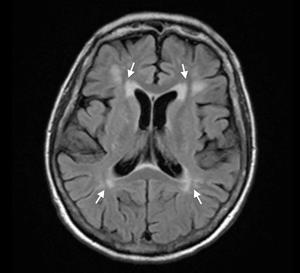

🧠 Neuroimaging:

● MRI Brain: Diffuse atrophy, periventricular white matter changes